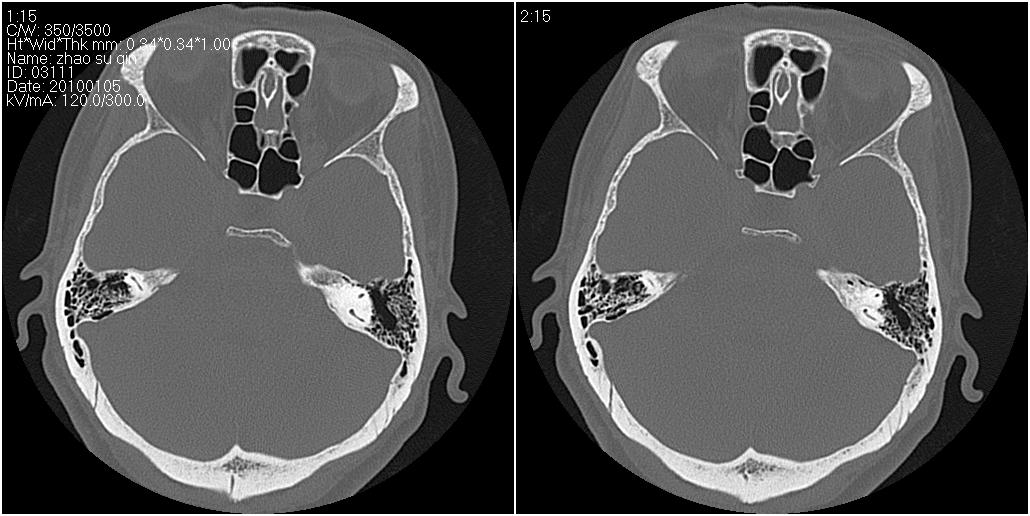

标题: CT24015:一个头部外伤患者进行鉴定,除了左侧筛板骨折,哪 [打印本页]

标题: CT24015:一个头部外伤患者进行鉴定,除了左侧筛板骨折,哪

看了几遍,其余未见明显骨折征。

1)左侧筛板骨折。2)双侧筛窦炎症(或积血)。

其余未见明显骨折征。